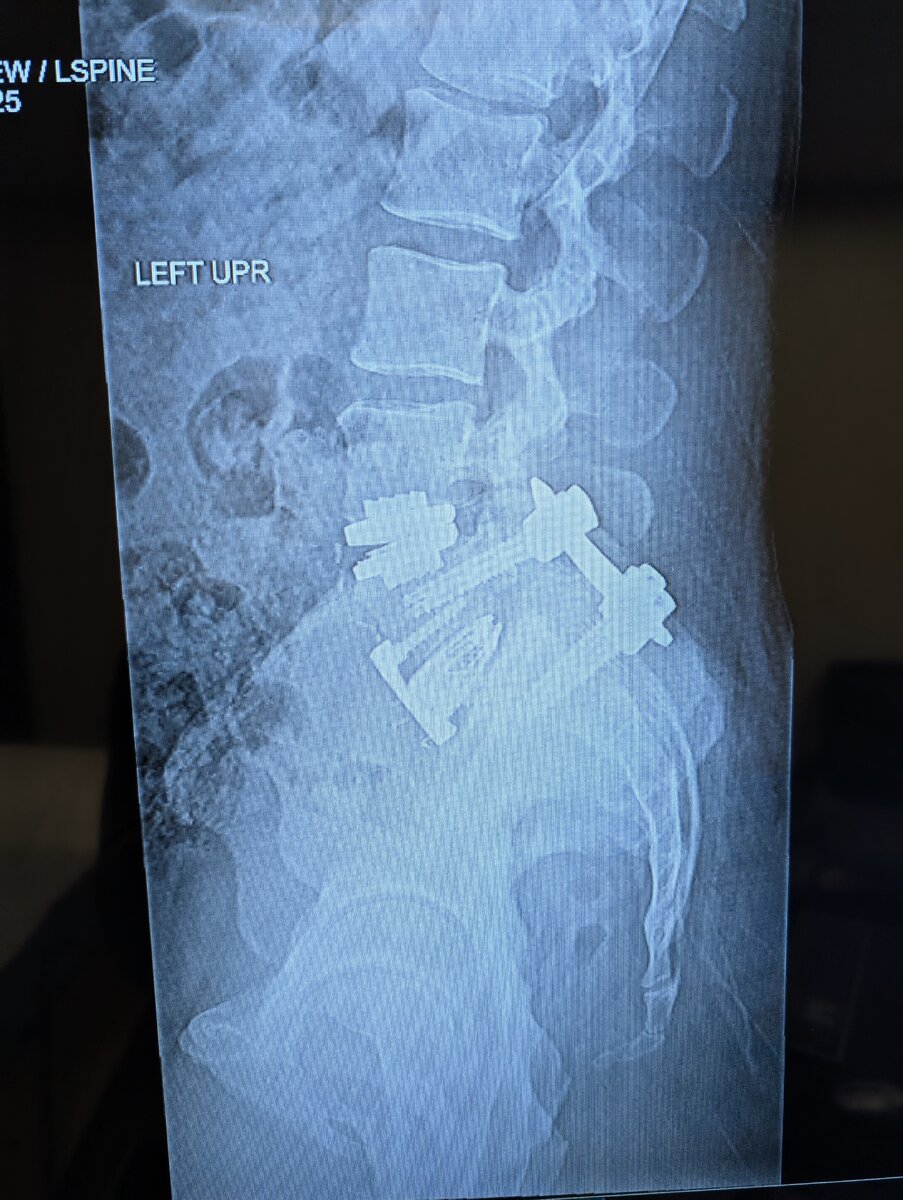

I got a spinal fusion and disc replacement two weeks ago and looks like everything has set well. I lifted and moved the last 20 years so not being able to bend, twist, or lift over 10 lbs until July sure will be a mental challenge.